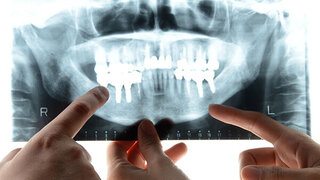

Weisheitszahn-OPDGMKG empfiehlt PRF zur Wundheilung Mit dem Einsatz von Eigenblut in Form einer PRF-Matrix lassen sich Schwellungen und Schmerzen nach der Weisheitszahn-OP reduzieren, teilt die Deutsche Gesellschaft für Mund-, Kiefer- und Gesichtschirurgie mit. 22.09.2022 ZahnmedizinChirurgie